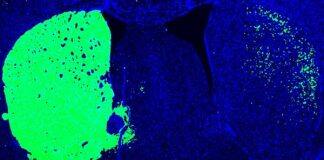

UC San Diego-Led Team Receives $9M to Advance Parkinson’s Disease Treatments

The grant from Aligning Science Across Parkinson’s (ASAP) will help further the discovery that inhibiting single gene in mice converts other cell types directly into new neurons, alleviating all Parkinson’s symptoms